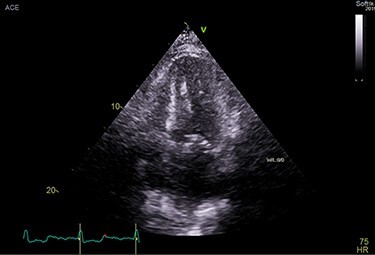

A 70-year-old African-American male, football coach presented with DOE. His PMH was notable for HTN, HLD, OSA, CAD s/p percutaneous coronary intervention (PCI), PN, CTS, permanent AFib. His lab results reported elevated NT-proBNP at 2369 pg/ml. TTE was suggestive of infiltrative cardiomyopathy (Fig. 9).

Figure 9 .

TTE showing increased myocardial echogenicity suggestive of ATTR-CA.

CMR showed late gadolinium enhancement in all four chambers, compatible with infiltrative cardiomyopathy. MM workup was negative. Endomyocardial biopsy was positive for amyloidosis. In addition, genetic testing for saliva was positive for ATTR. The patient was started on tafamidis for ATTRwt-CA in addition to the treatment of CHF and AF. His SOB and chest discomfort improved at the 3-month F/U visit.